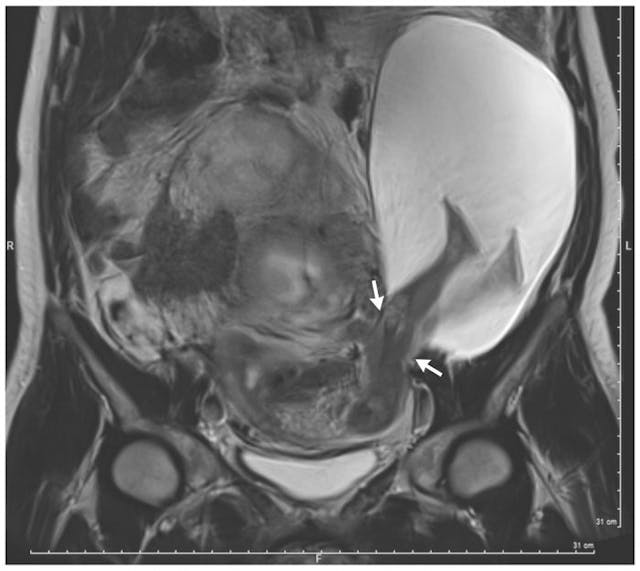

The mother’s ultrasound, showing her son’s legs sticking out of her womb

Dr. Pierre-Emmanuel Bouet, an obstetrician at the University of Angers Hospital Center, says he was shocked when he discovered a medical anomaly via ultrasound in one of his patients, a 33-year-old pregnant woman. The woman had an inch-long rupture in her uterus, and the baby’s legs were sticking out through it. Bouet told The Washington Post that such cases are extremely rare, with this instance representing only the 27th such recorded case.

While most women with uterine ruptures may experience pain and internal bleeding, Bouet says that in this case, the baby’s legs (along with the amniocele) served to plug the rupture, blocking internal bleeding. Despite the lack of internal bleeding, risks were still present. In a report on the case published last week in The New England Journal of Medicine, Bouet and colleague Dr. Charlyne Herondelle explained, “The patient and her partner were informed of the potential risks of these findings, including complete uterine rupture [which can suffocate the baby due to a lack of oxygen], placenta accreta, hysterectomy, and preterm birth.”